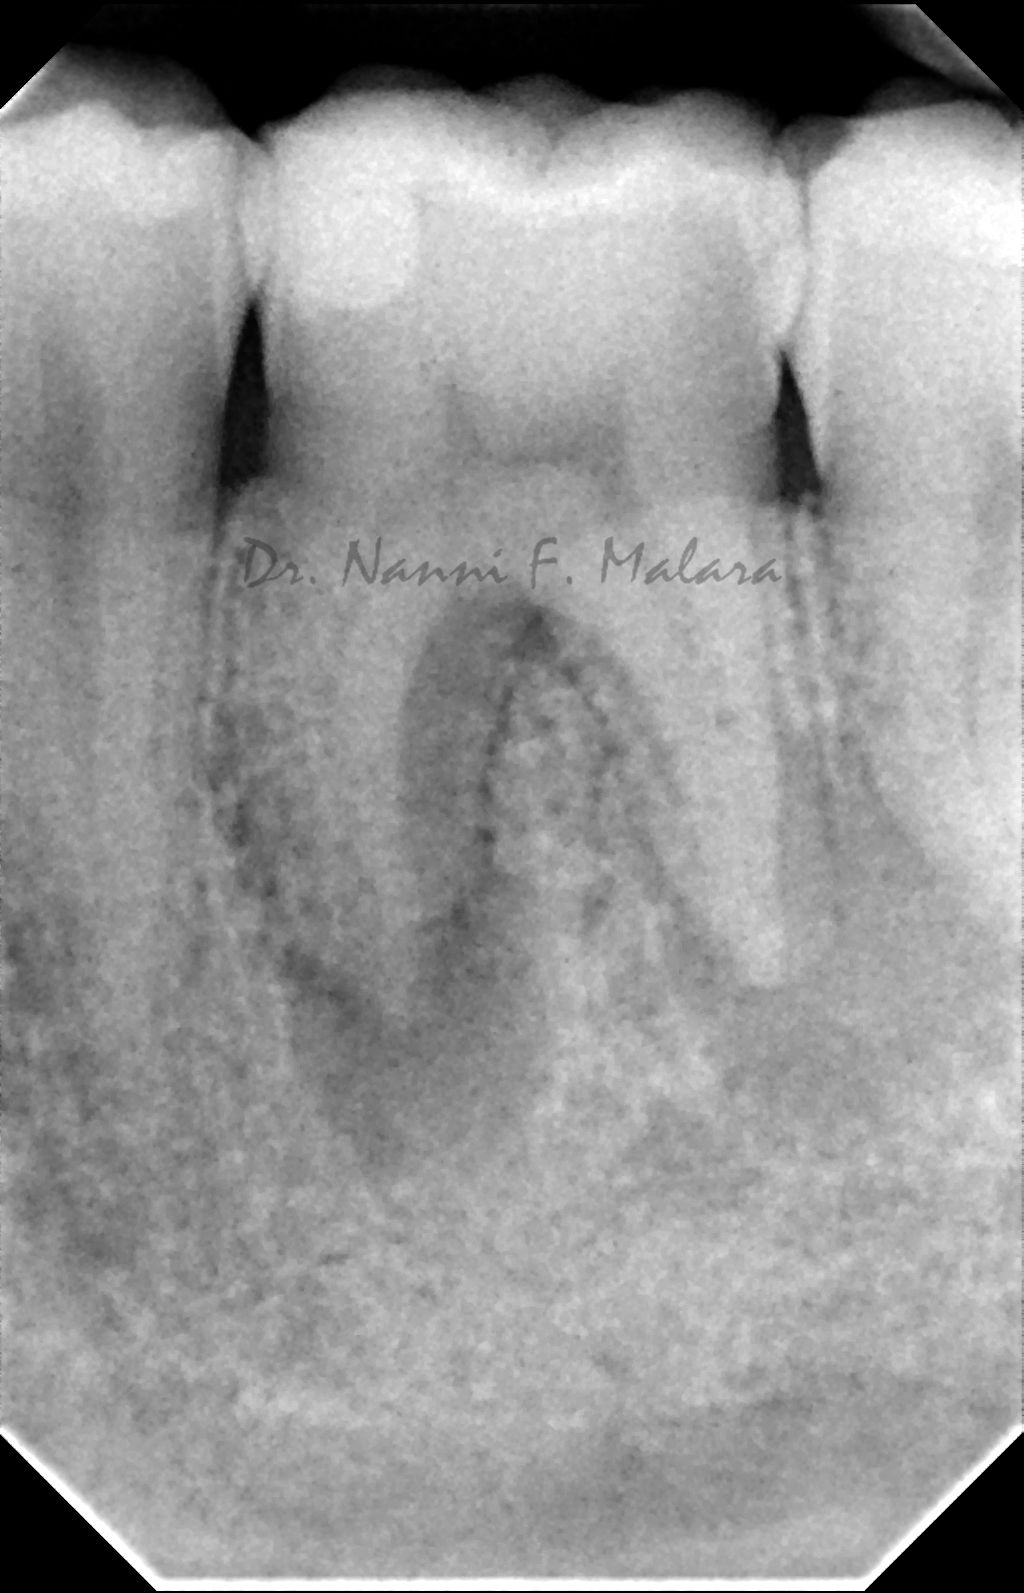

Il controllo radiografico eseguito ad 8 mesi evidenzia l'avvenuta guarigione con il riassorbimento completo della lesione apicale.